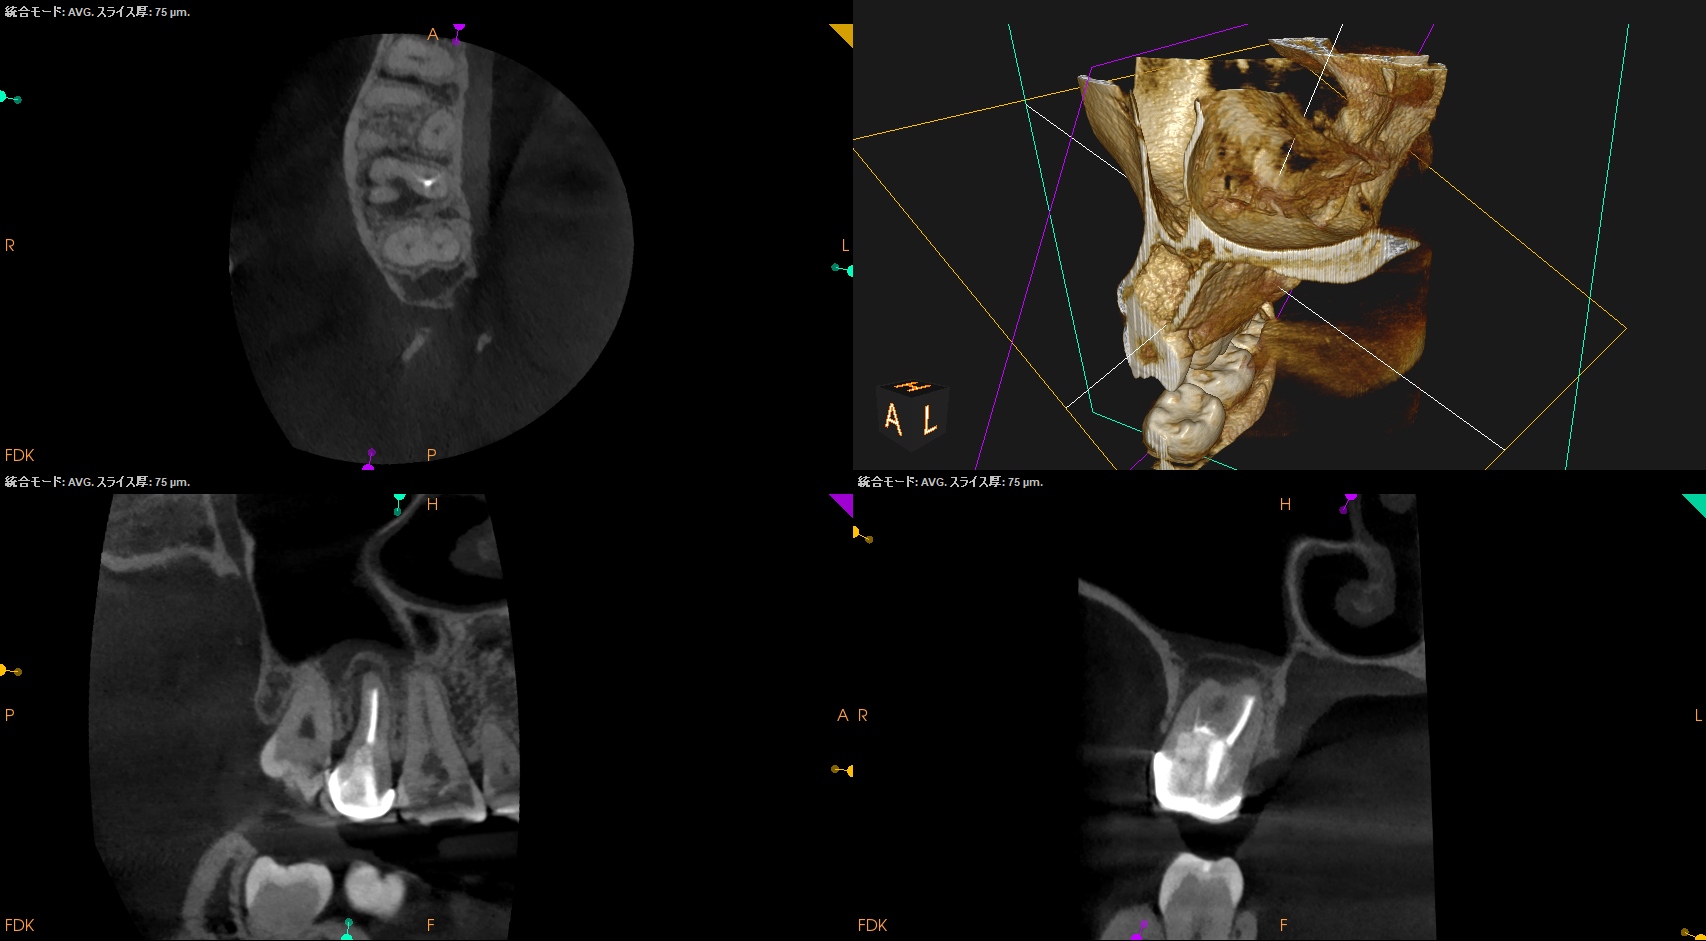

CBCT(2025.11.11)

MB

DB

P

根管は石灰化&すでに拡大済みであるので、再根管治療ではなく外科治療、つまり、Intentional Replantationの適応症である。